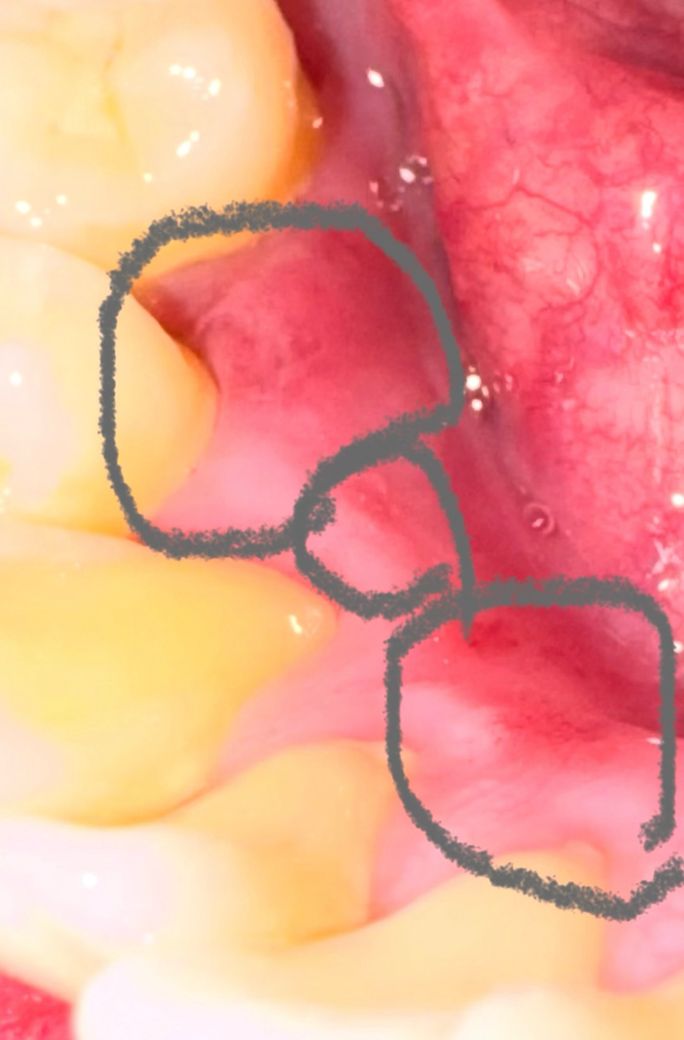

(재업) 아래안쪽 잇몸이 까짐(상처)이 생겼는데 봐주세요

엊그제부터 아래 안쪽 잇몸에 몇군데가 잇몸이 까진

느낌?(상처)가 생겼는데 동그랗게 조금씩 잇몸이 까진느낌

음식물이 닿을때마다 통증도

조금씩있고

주변 잇몸이 들떠있는? 느낌이 나는데

일단 오라메디연고 바르면서 지켜볼까요?

구내염처럼 까진부분이 튀어나오거나 만졌을때 수포?

그런게 만져지지는 않는데 전문가분들 상황좀 한번

봐주세요.

(현재 감기에걸려서 감기약을 일주일째 복용중입니다.)

• 1번 째 사진